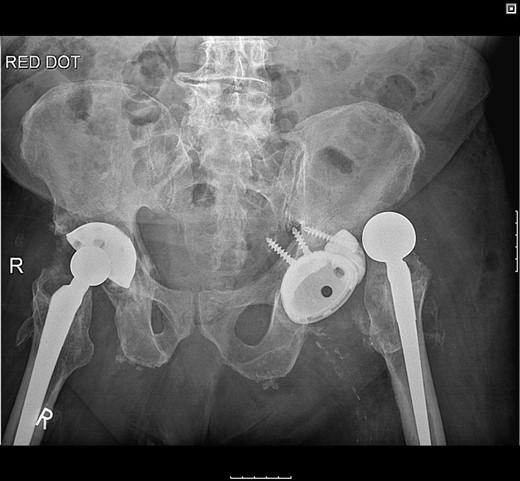

The femoral stem was kept firm in its proper position. Structural porous titanium acetabular augment (Regenerex™), reinforced with a cancellous allogeneic bone graft, was used to reconstruct the superior acetabular wall. The cup was completely revised using a Biomet® Regenerex Ringloc® multihole 56-mm acetabular cup and a Hi-wall Ringloc-x PE 54-mm liner. The previous 32-mm femoral head was replaced with a Bioball® 36-mm metal head and a Bioball® adapter standard (0 mm) Taper 11/13 (4° 3°), correcting the offset and achieving stability (Fig. 4).

A post-revision radiograph demonstrating a structural graft using the acetabular augment (Regenerex™) and revised cup in situ.

Postoperatively, the patient fell on the ward resulting in posterior dislocation (Fig. 5) requiring an open reduction. Subsequently, the patient developed a superficial surgical site infection, which resolved with antibiotic therapy. Three months following discharge, the patient was pain-free and could ambulate with a Zimmer frame.

Radiograph following postoperative fall demonstrating posterior dislocation.